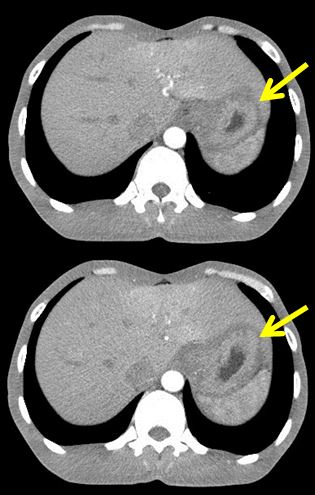

Trước hóa trị

Khối u thâm nhiễm tổ chức xung quanh | Sau 6 đợt hóa trị

Thành dạ dày bờ không đều, không còn thâm nhiễm tổ chức xung quanh |

Hình 4: Kết quả chụp CT bụng trước và sau 6 đợt hóa trị.